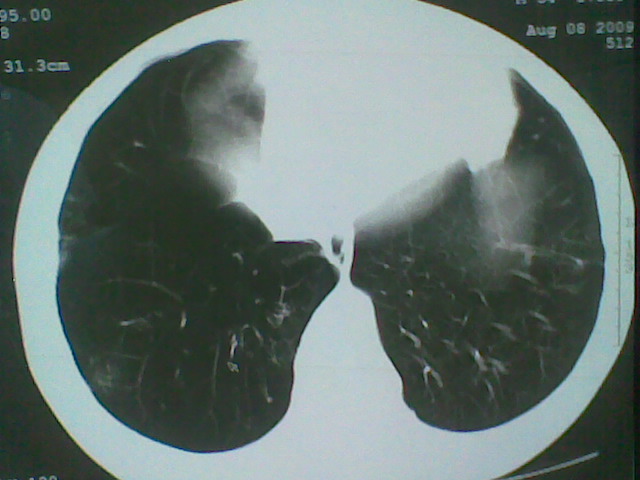

标题: CT21512:支扩伴感染?

患者女。咳嗽数天,咯血半天。

我们报的是支扩伴感染?

支持楼主意见,还有肺气肿